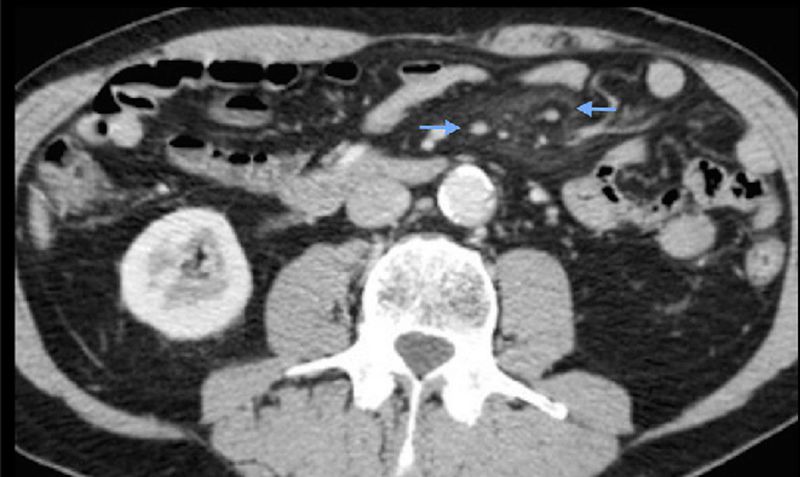

A 65 yrs man presented to the hospital with abdominal mass and pain. In the CT we have found this.

What's your dx and what are the pointed area?

Mesenteric lymphadenitis?